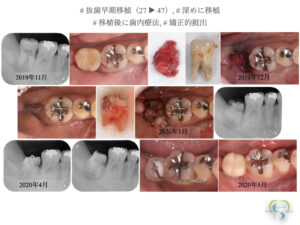

‎20260312_自家歯牙移植.‎003 | さとう歯科クリニック 南区妹尾